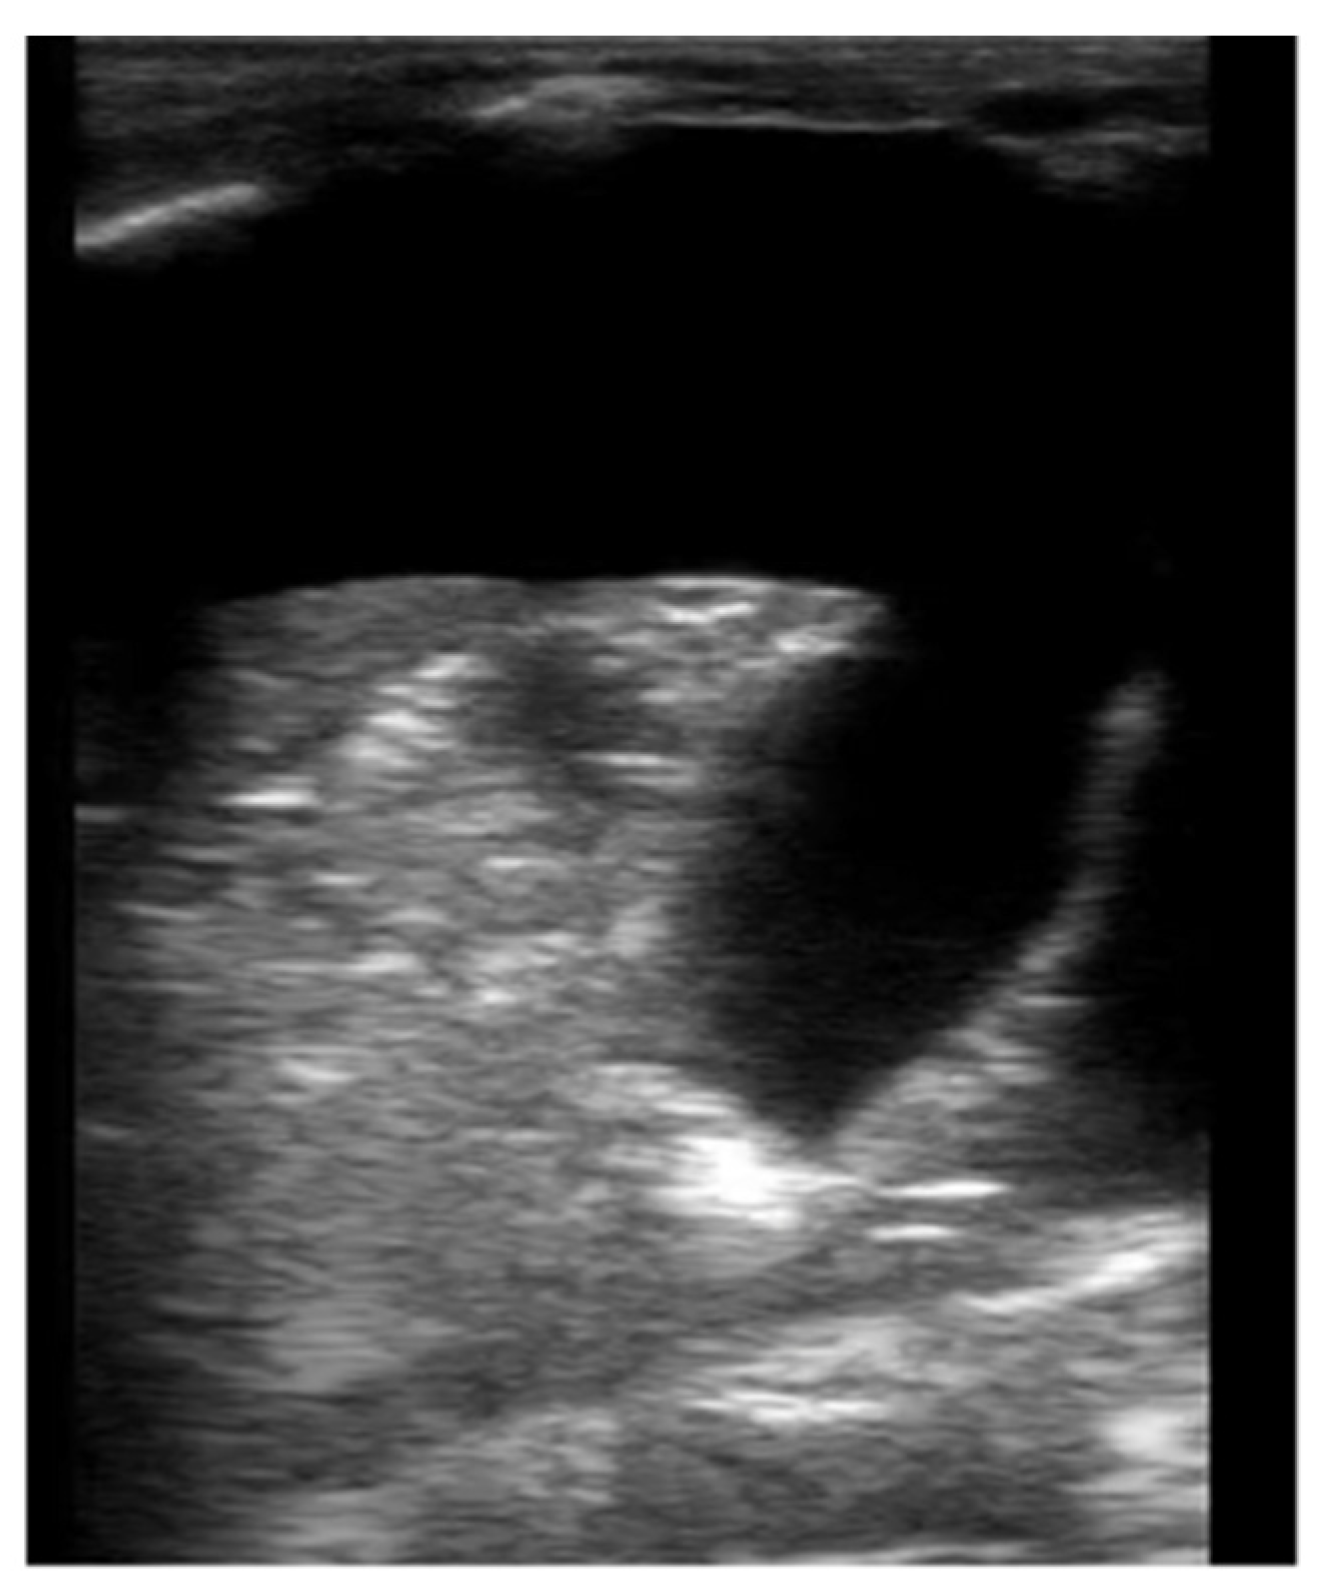

Figure 4. Large pleural effusion in B-mode. Large pleural effusion with septation and complete atelectasis of the lung.

Neonatal LUS can detect small volume effusions and can be used to guide thoracentesis [25]. In B-mode, the transudate fluid is anechoic, and the lung parenchyma can be visualized as hepatization of the lung (Figure 4, Supplementary Materials Video 2). In M-mode, the sinusoid sign can sometimes be visualized where the visceral line moves towards the pleural line with respiration. Color doppler can also be used to evaluate echogenic vs. solid collections within the effusion, however this is not commonly used in neonatal LUS.